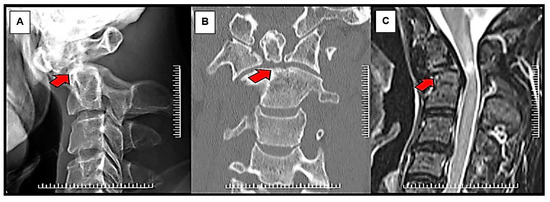

Before surgery, all patients had a standard series of radiographs, including the open mouth, anterior-posterior, static lateral, and dynamic lateral flexion/extension views. The lateral flexion-extension view was used to evaluate the instability of the C1-C2 complex, including the possibility of reduction that could be achieved intraoperatively. Excessive C1-C2 translation and lateral atlantodental interval more than 3 mm generally caused instability. Thus, in this case, the fusion of C1-C2 joints should be carried out. Computed tomography (CT) scan and magnetic resonance imaging (MRI) were also performed to evaluate further the bony anatomy detail of the upper cervical spine, the spinal cord, and the vertebral artery status (Figure 1). In our institution, the type of surgical fixation, either Magerl’s C1-C2 transarticular screw fixation technique augmented with supplemental wiring or Harms-Goel C1-C2 screw-rod segmental fixation technique, was selected based on local management protocol, which considered the width of the C2 isthmus, the vertebral artery pathway, and the presence or absence of a kyphotic back. Magerl’s C1-C2 transarticular screw fixation technique would be chosen for patients with a C2 isthmus wider than 3.5 mm, absence of anomalous vertebral artery pathway, and no kyphotic back. Harms-Goel C1-C2 screw-rod segmental fixation technique was performed in the rest of the patients who were not indicated for Magerl’s C1-C2 transarticular screw fixation technique (Figure 2).

Figure 3. Radiographic images of patients with reducible nonunited type II odontoid fracture with myelopathy treated with (A) Magerl’s C1-C2 transarticular screw fixation technique augmented with supplemental wiring and (B) Harms-Goel C1-C2 screw-rod segmental fixation technique. Coronal CT scan imaging (C) shows C1-C2 complex screw construction with solid fusion mass in Harms-Goel C1-C2 screw-rod segmental fixation technique at 3-month follow-up.